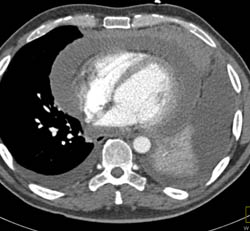

Left Atrial Thrombus